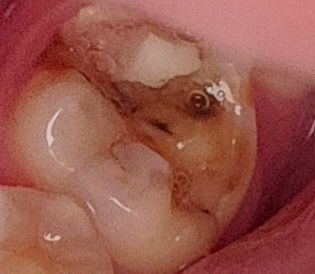

(직접 찍은 치아 사진 포함) 혹시 이정도의 치아 깨짐은 어떤 치료를 받게 되나요?

예전에 치과가서 때운게 최근에 떨어졌다가 오늘은 이가 깨져버렸네요 이거 혹시 치료 받는다면 어떤 치료를 받게되나요 아니면 제가 월요일에 치과를 방문할 예정인데

치료 받은곳만 저렇게 깨진거라면 신경치료를 하시고 크라운 치료를 하셔야될것같습니다. 하지만 뿌리까지 깨졋다면 발치를 해야될 가능성도 있습니다.

치아 파절부위가 넓다면 크라운 치료를 하게 됩니다

파절된 부위가 치조골 아래로 진행이 되었다면 발치를 해야하는 경우도 생깁니다